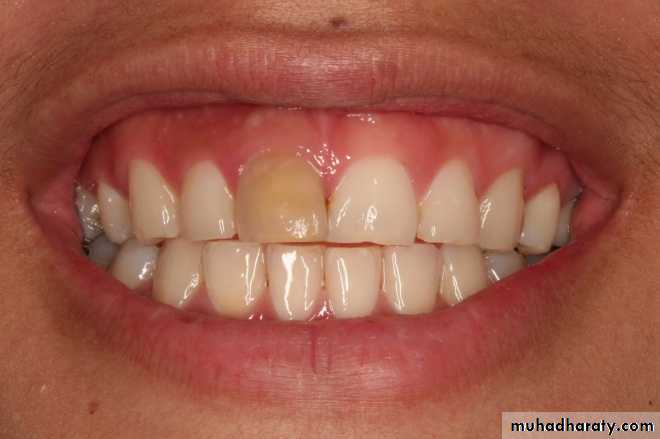

• Discoloration of tooth—First indication of pulp death

5. Visual examination:Tooth shows color change like dull or opaque appearance due to lack of normal translucency

• “Pink Tooth” is the pathognomic feature of internal root resorption (especially in the crown).

• Clinically:“Pink Tooth” appearance• Radiographic changes:

• When external root resorption extends to crown, it gives “Pink tooth” appearance